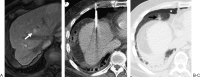

Radiofrequency ablation (RFA) is an alternative therapy for hepatocellular carcinoma and liver metastases when resection cannot be performed or, in the case of hepatocellular carcinoma, when transplant cannot be performed in a timely enough manner to avoid the risk of dropping off the transplant list. RFA has the advantage of being a relatively low-risk minimally invasive procedure used in the treatment of focal liver tumors. This review article discusses the current evidence supporting RFA of liver tumors, as well as the indications, complications, and follow-up algorithms used after RFA.